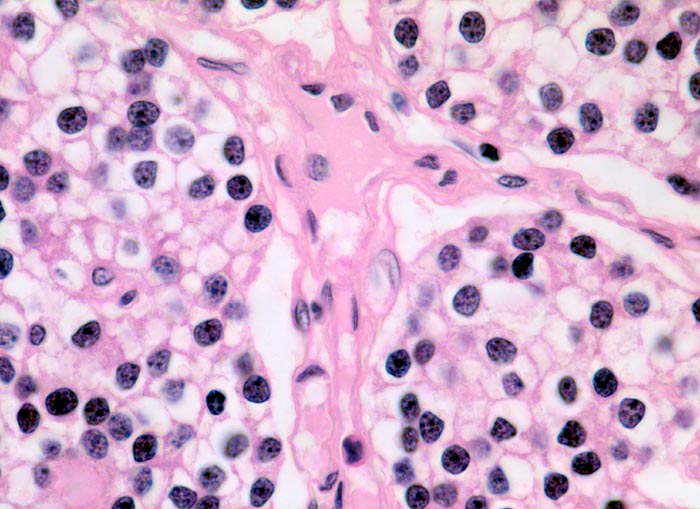

Morphologie der Nebenschilddrüsenhyperplasie:

Morphologisch besteht bei sHPT eine Hauptzellhyperplasie. Makroskopisch findet sich eine meist ungleich ausgebildete Vergrösserung aller Nebenschilddrüsen. Die Grösse der Drüsen entspricht der Schwere und der Dauer des Stimulus. Die im früheren Stadium gefundene diffuse Hyperplasie mit Ersatz des Stromas und der Fettzellen durch chronisch stimulierte Hauptzellen (> 558) (> 559) geht im späteren Stadium in eine noduläre Hyperplasie („Pseudoadenome“) über (> 2358). Die regulierte Anpassung der Nebenschilddrüsen kann in eine Autonomie übergehen (tHPT) (> 3704). Morphologisch besteht in diesem Fall eine unregelmässige noduläre Hyperplasie. Gelegentlich entwickelt sich beim tHPT ein dominanter Knoten, der morphologisch nicht von einem Adenom bei pHPT unterscheidbar ist.

Morphologische Merkmale:

• Knotige vergrösserte Nebenschilddrüse. Abgrenzung der einzelnen Knoten durch breite Fibrosebänder.

• Hyperplasie lipidarmer Hauptzellen.

• Areale mit oxyphilen Zellen.

• Verminderter Fettgehalt (<<35%). Für normale Nebenschilddrüsen gilt: